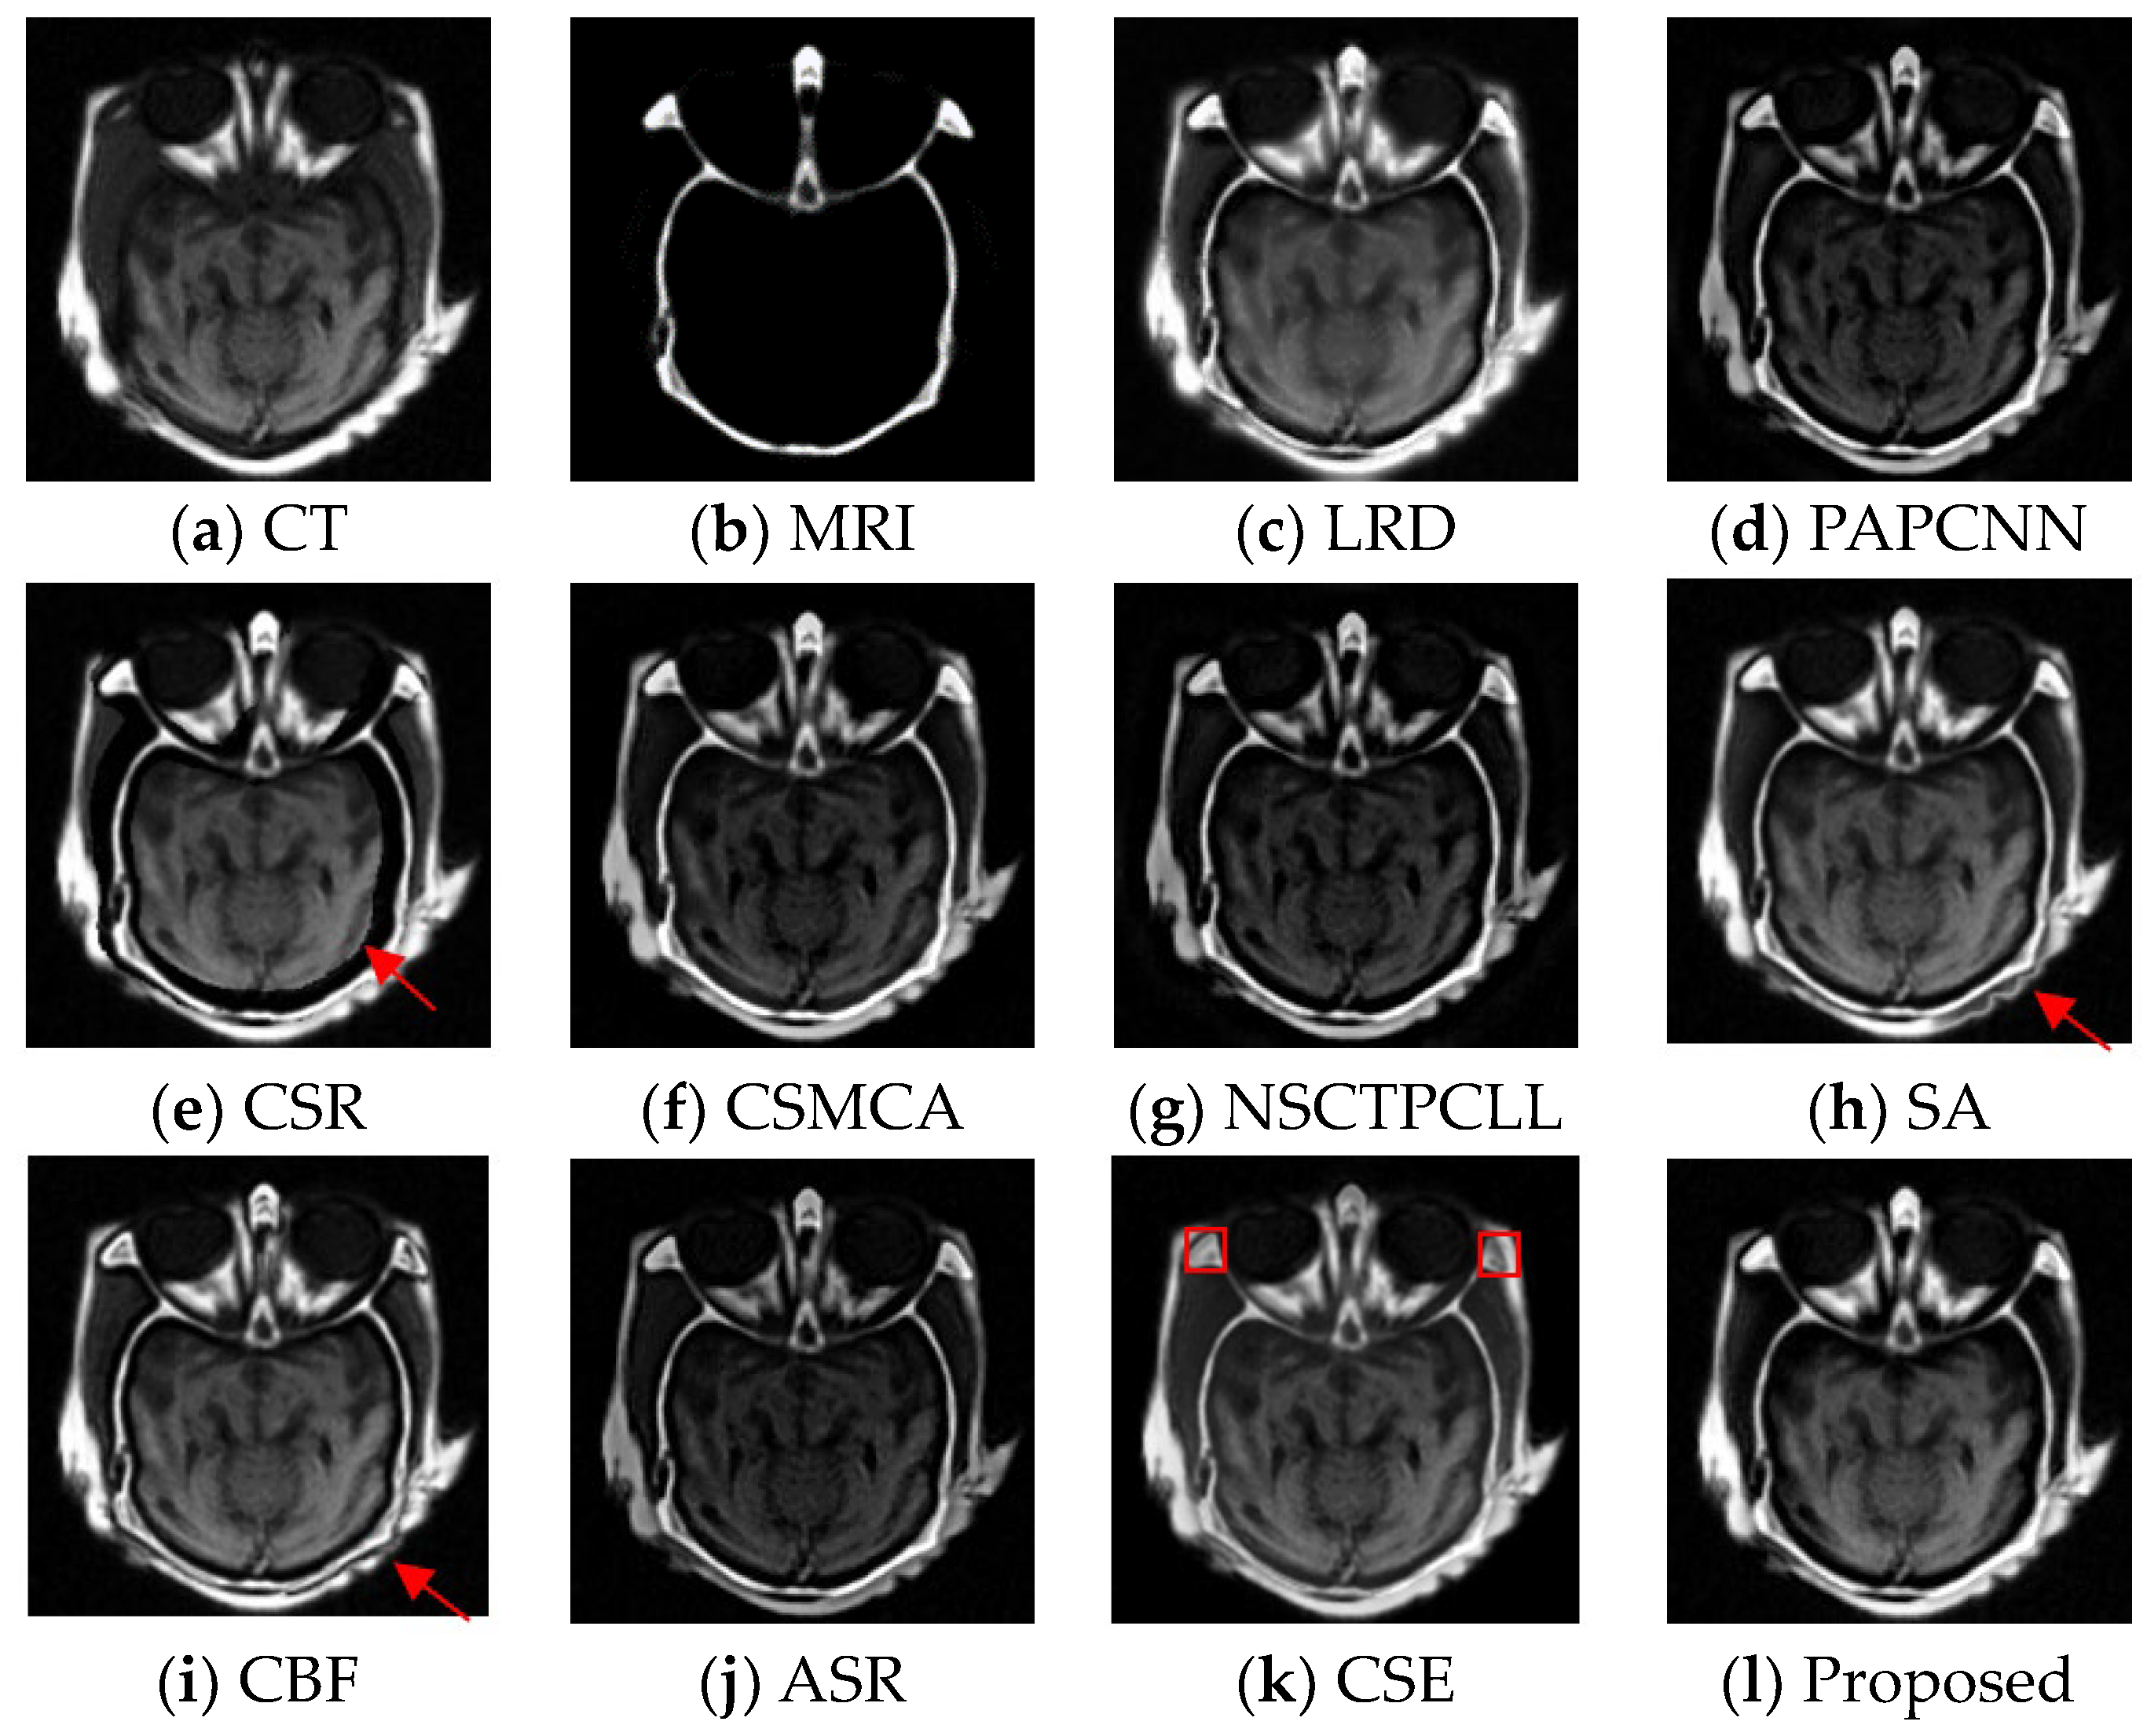

4.4. Experimental Results